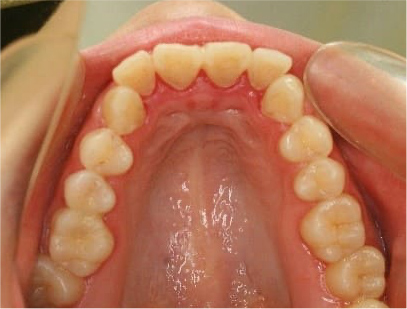

• 上側